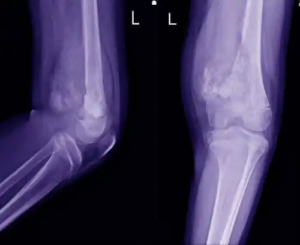

Diagnosen ställer en läkare vanligtvis på basis av en klinisk intervju och hälsoanamnes, tillsammans med några tester. Det börjar oftast med röntgen, som kompletteras med en MR-undersökning. Läkaren kommer att beställa en biopsi så snart hen upptäcker ett problem och kan identifiera området för detta.